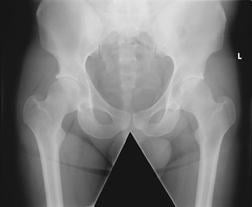

October 14, 2011 — A study published in the September/October issue of Radiologic Technology shows increasing the source-to-image distance for direct digital radiography (DR) pelvic examinations reduces radiation dose while maintaining image quality. RT is a journal of the American Society of Radiologic Technologists (ASRT).

To perform the study, the researchers positioned an anthropomorphic pelvic phantom for a standard anteroposterior examination. Using a single DR unit with a flat panel detector, they set an initial source-to-image distance of 100 cm and used an antiscatter focused radiation grid. The x-ray beam was collimated for a standard AP pelvic examination and was kept constant throughout the experiment, while source-to-image distance varied from 80-147 cm.

Two exposures were taken in 10-cm intervals to determine image quality, and the experiment was repeated without the grid. A total of 80 images were then sent to a reporting-grade picture archiving and communication workstation for image quality analysis. Researchers calculated the entrance surface dose and effective dose based on distances of 60 cm, 80 cm, 100 cm, 120 cm, 140 cm and 147 cm.

The research results indicate that by increasing the source-to-image distance, both the entrance surface dose and effective dose decreased when using the antiscatter radiation grid; they decreased further when the grid was removed. At 147 cm, the decrease in entrance surface dose and effective dose when using a grid equated to a 25 percent reduction in radiation dose compared with standard parameters.